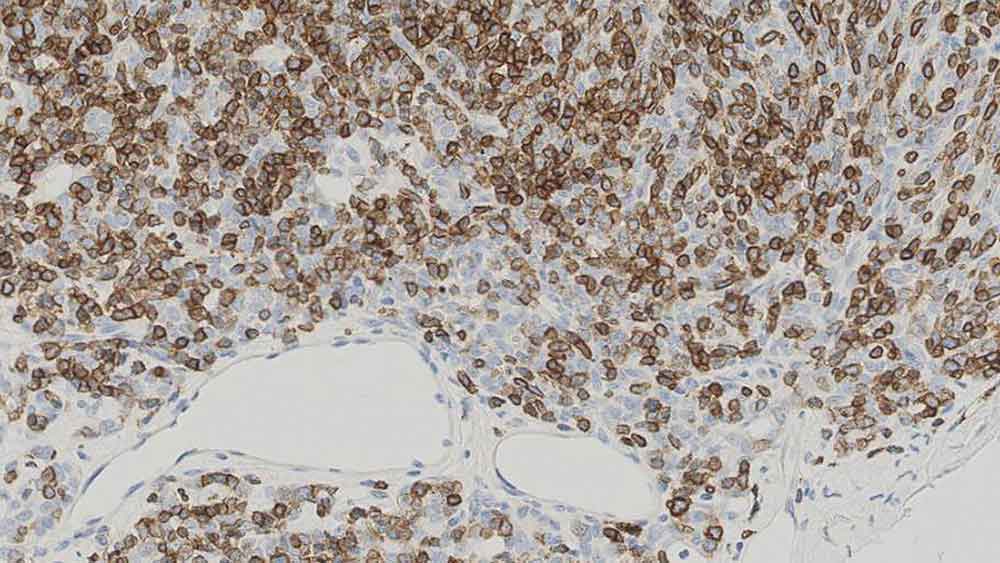

Human thymoma: immunohistochemical staining for CD1a. Note the neoplastic cells show a moderate to strong and distinct membrane staining reaction. CD1a: clone MTB1

CD1a ist ein Protein von 43 bis 49 kD, das auf dendritischen Zellen und kortikalen Thymozyten exprimiert wird. Es wurde aufgezeigt, dass die CD1a-Antigenexpression bei der Differenzierung zwischen Langerhans'schen Zellen, in der Haut und im Epithel vorhandenen leistungsfähigen Antigen-präsentierenden Zellen und interdigitierenden Zellen hilfreich ist. In immunhistochemischen Studien über das CD1a-Antigen wurde neben einem Rückgang der epidermalen Langerhans'schen Zellen bei der Transplantat-Wirt-Reaktion auch die Beteiligung von CD1a-Antigen-positiven dendritischen Zellen bei der Entstehung atherosklerotischer Läsionen und asthmatischen Entzündungsreaktionen aufgezeigt. Klon MTB1 erkennt kortikale Thymozyten, Langerhans'sche Zellen in der Epidermis sowie interdigitierende Zellen der Dermis und des geschichteten Plattenepithels in den Tonsillen. Klon MTB1 kann auch kleine isolierte Lymphozytengruppen außerhalb der Keimzentren der Tonsillen nachweisen, was auf eine gewisse Kreuzreaktivität mit dem CD1b-Antigen schließen lässt. Auch Klon JPM30 weist kortikale Thymozyten, Langerhans'sche Zellen in der Epidermis, interdigitierende Zellen der Dermis und des geschichteten Plattenepithels in den Tonsillen nach, färbt aber darüber hinaus auch Schweißdrüsengänge in der Dermis und Epithelzellen des Dünndarms, ein Hinweis auf eine Kreuzreaktivität mit dem CD1d-Antigen.